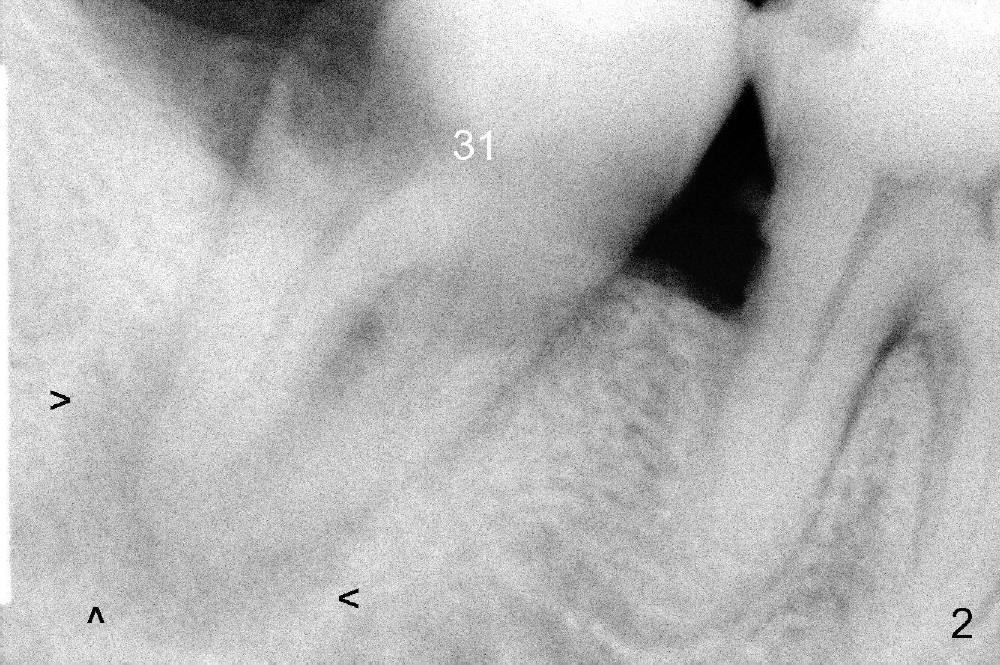

A 52-year-old man (heavy smoker) presents to office without schedule.  He has severe pain at #31 and wants extraction immediately (Fig.1,2).  He likes the idea of immediate implant, but we do not have time for it that day.  Therefore the tooth is extracted (Fig.3).  The socket is single.  After debridement, bone graft (Fig.5 *) and collagen membrane (Fig.4) are placed.

The patient will return for implant placement 2.5 months post extraction.  He must be a gagger, because PAs in Fig.2,5 are taken with sensor 1.  The Inferior Alveolar Nerve is out of view.  It appears that he is too busy to have CBCT taken in the other office.